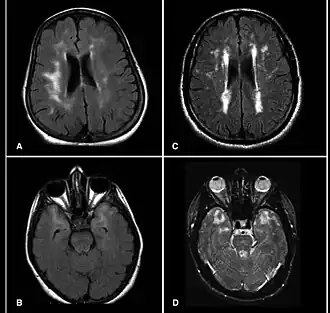

Per sindrome CADASIL (acronimo derivante dai termini in inglese "cerebral autosomal dominant arteriopathy with subcortical infarcts and leukoencephalopathy", in italiano "arteriopatia cerebrale autosomica dominante con infarti sottocorticali e leucoencefalopatia"), chiamata anche demenza-infarto cerebrale multiplo ereditario o demenza ereditaria con infarti cerebrali multipli[1], si intende una malattia di carattere autosomico dominante dei piccoli vasi caratterizzata da ripetuti infarti cerebrali profondi.

La malattia, in seguito ai continui ictus ed emorragie cerebrali, giunge in fase acuta e progredisce quindi con demenza di tipo vascolare e subcorticale progressiva, associata a paralisi pseudobulbare, incontinenza urinaria, episodi frequenti di stato confusionale, declino cognitivo, atassia, disturbi muscolari e sensitivi di tipo neurologico, arrivando - in certi casi di lunga sopravvivenza - all'apatia, alla paraplegia e alla totale catatonia. La morte avviene per possibili diverse cause: ictus, paralisi avanzata, disturbi circolatori e respiratori, o infezioni sopraggiunte.[3][4] La sopravvivenza dalla diagnosi va da pochi anni a più di vent'anni; la sopravvivenza delle femmine è più lunga dei maschi.[3]